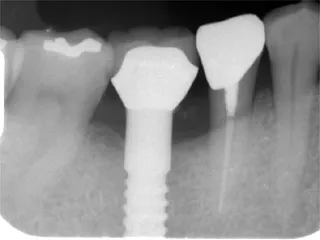

| 自費治療 インプラント |

治療前

インプラントは第二の歯とも呼ばれ 顎の骨に金属製のネジを立てて 人工の歯を取付けます 当院では高い技術と経験で対応しています ■長所 ・しっかり噛むことができる ■短所 ・禁忌症がある ・高い インプラント・くわしく |